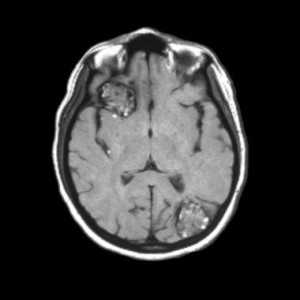

![кавернозная ангиома мрт]()

МРТ-признаки кавернозной ангиомы. Крупные кавернозные ангиомы правой лобной доли и левой затылочной доли на Т1-взвешенном аксиальном срезе. У этих двух гетерогенных объемных образований отмечается сетчатая структура центральной части с чередованием участков высокой и низкой интенсивности сигнала, окруженная гипоинтенсивным ободком из гемосидерина.

Свежая гематома, содержащая дезоксигемоглобин, изоинтенсивна на Т1-взвешенных изображениях и значимо гипоинтенсивна на Т2-взвешенных изображениях. Подострая гематома, содержащая внеклеточный метгемоглобин, гиперинтенсивна как на Т1-, так и на Т2-взвешенных изображениях вследствие парамагнетического эффекта, оказываемого метгемоглобином.

Промежуточные фиброзные элементы характеризуются слабо гипоинтенсивным сигналом на Т1- и Т2-взвешенных изображениях, поскольку содержат кальцификаты и гемосидерин. Гетерогенная внутренняя часть образования окружена гемосидериновым ободком, обладающим низкой интенсивностью на Т1-взвешенных изображениях. Гипоинтенсивность этого ободка становится более выраженной, напоминающей ореол, на Т2-взвешенных изображениях и изображениях в режиме градиентного эха благодаря более высокой чувствительности этих последовательностей к изменениям магнитного поля.